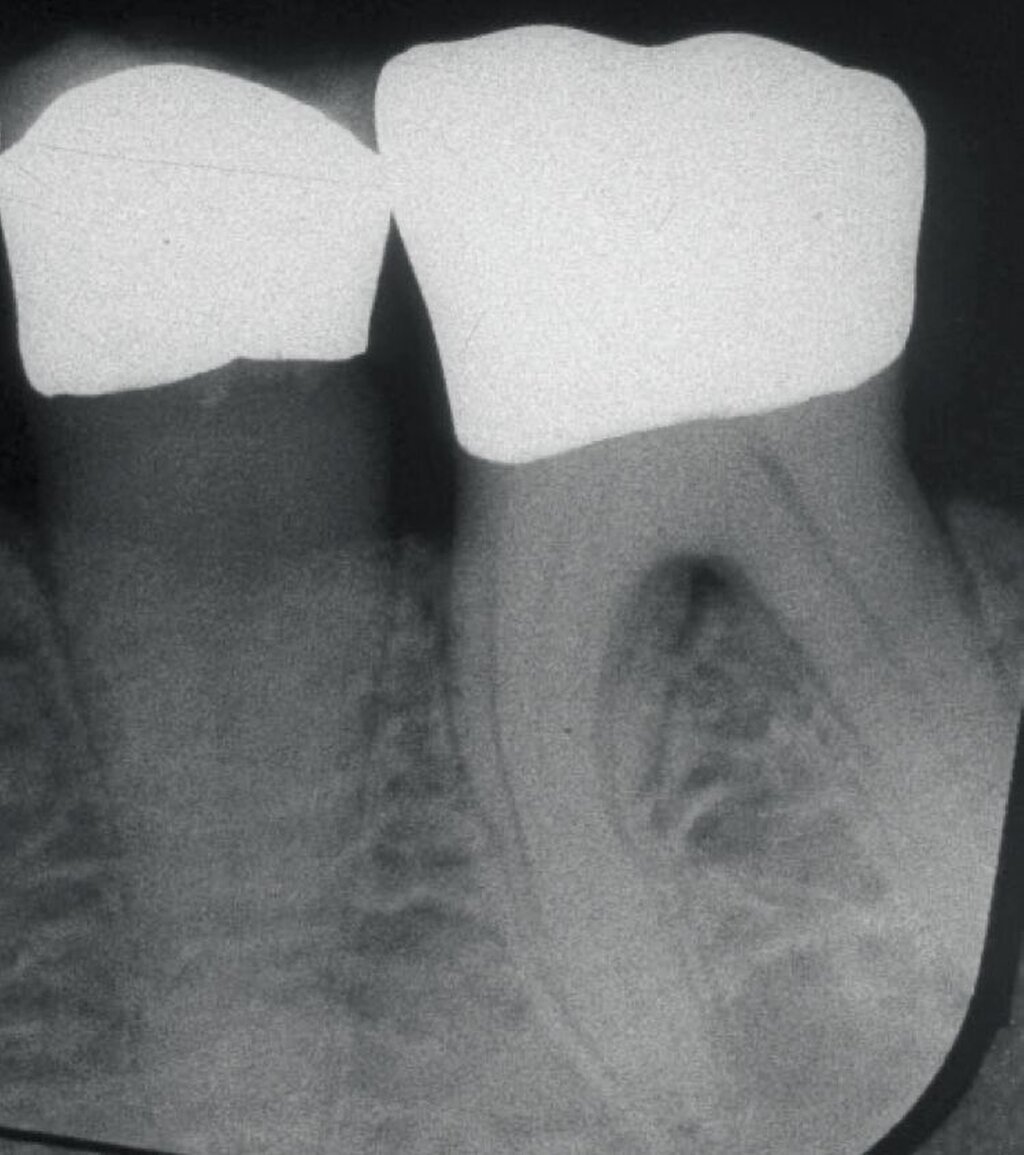

Da der histologische Nachweis einer erfolgreichen Furkationsregeneration kein praktikabler Endpunkt für kontrollierte klinische Studien ist, dienen Veränderungen bei direkten Knochenmessungen (offene Messungen: horizontales Knochensondierungsniveau bei der Operation und während eines „Re-entry“-Eingriffs) als primäre Ergebnisvariablen zur Bewertung des klinischen Erfolgs, während geschlossene Messungen wie der klinische Attachmentgewinn (horizontales/vertikales Attachmentniveau (CAL)), die Reduktion der Taschensondierungstiefe (TST) und röntgenologische Beurteilungen als sekundäre Zielparameter dienen können [Machtei, 1997]. Zu den von den Patienten berichteten Ergebnissen nach einer regenerativen Furkationschirurgie können postoperative Schmerzen, die Komplikationsrate, der wahrgenommene Nutzen und die Veränderung der Lebensqualität gehören.

Ein adäquater Zugang zum Operationsbereich und auch für die zukünftigen Mundhygienemaßnahmen ist äußerst wichtig. Molaren mit Grad-II-Furkationsdefekten (mandibulär und bukkal maxillär) sind Kandidaten, die für ein regeneratives Verfahren infrage kommen. Basierend auf der verfügbaren Evidenz sind interdentale Grad-II-Furkationsdefekte an Oberkiefermolaren deutlich weniger geeignet, höchstwahrscheinlich aufgrund des eingeschränkten Zugangs. Weitere lokale Charakteristika können Auswirkungen auf die Ergebnisse der regenerativen Furkationschirurgie haben. Zum Beispiel können ein dickerer Phänotyp und das Fehlen einer Weichgeweberezession die Heilung nach GTR-Verfahren positiv beeinflussen. Günstigere Ergebnisse sind an Stellen zu erwarten, an denen das verbleibende approximale Knochenniveau koronal zum Eingang beziehungsweise zum Dach des Furkationsdefekts liegt, verglichen mit solchen, bei denen das approximale Knochenniveau auf der Höhe oder apikal des Furkationseingangs liegt. Ein enger interradikulärer Abstand kann eine gründliche Defektinstrumentierung beeinträchtigen. Das Vorhandensein einer Wurzelkanalfüllung ist nicht per se eine Kontraindikation für die Furkationsregeneration – vorausgesetzt, es gibt keine Anzeichen für apikale pathologische Veränderungen.

Fall 1 – einfach

Fall 2 – fortgeschritten

Fall 3 – komplex